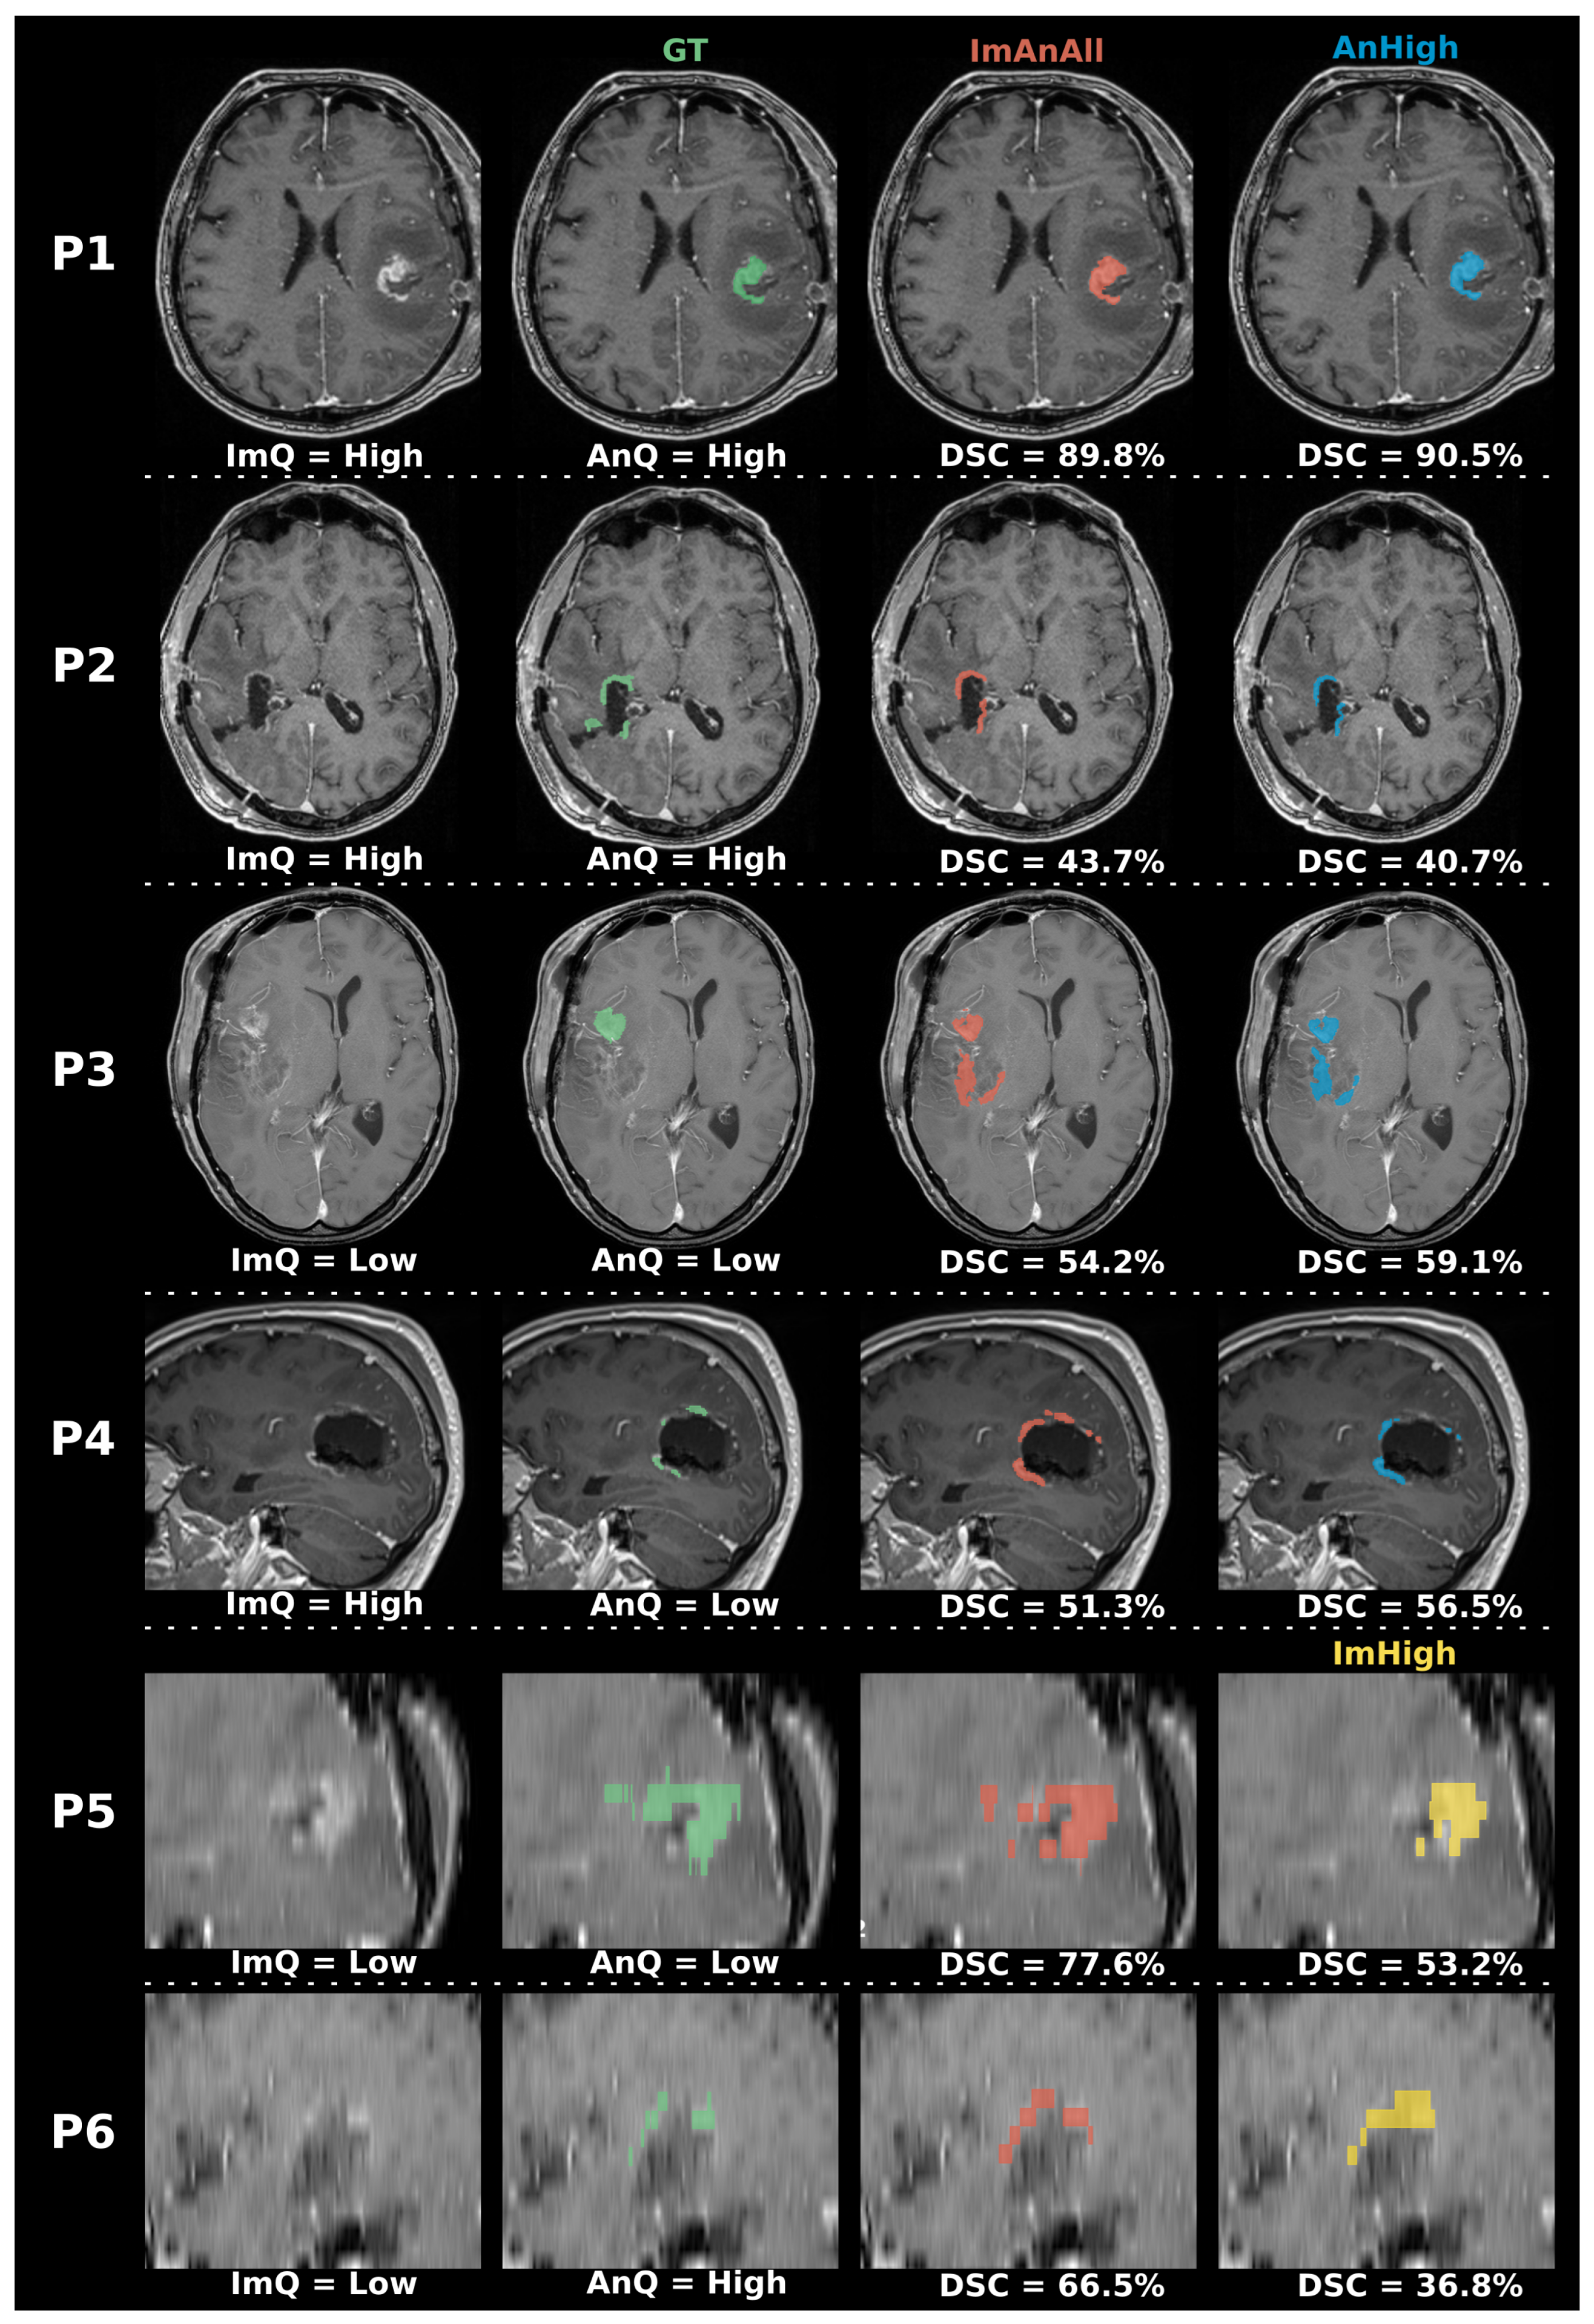

- ImAnAll: The whole dataset. This was used as the reference model to compare the other models against.

- ImHigh: High-quality T1-CE images, irrespective of the annotation quality.

- AnHigh: High-quality annotations, irrespective of the image quality.

- ImAnHigh: Intersection of high-quality T1-CE images and high-quality annotations.